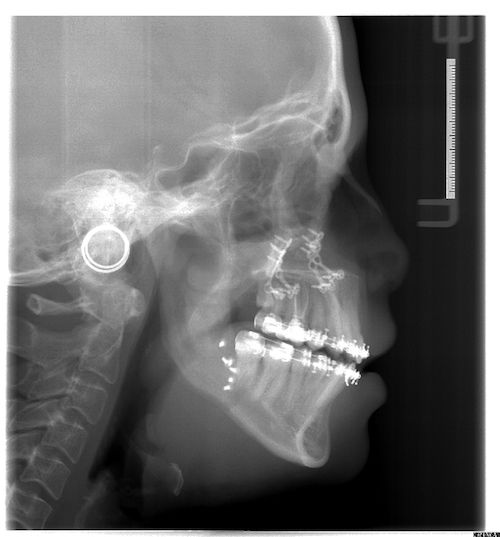

Surgery may involve either the upper jaw, lower jaw or both depending on the skeletal discrepancy of your particular case. This will allow the teeth to meet correctly and provide you with an improved bite, and often there is an accompanying improvement in your facial appearance and profile.

This will vary according to the type of surgery that has been planned by Mr Duncan’s team. All the incisions are carried out inside the mouth apart from 2 very small 2-3mm scars in both cheeks at the angle of your jaw (only if lower jaw surgery is carried out). Prescription bone cuts are then made and your jaws are moved into their planned position relative to each other. They are then secured in position with either titanium mini plates or screws, which stay in permanently unless they become loose or infected. The soft tissues are then sutures together with dissolving stitches, which do not need to be removed, and should dissolve themselves within 3 weeks.

You may need multiple extractions prior to surgery – orthodontic extractions are required to make space to align teeth, ready for the surgery. Lower wisdom teeth ideally need to be removed 6-9 months prior to any lower jaw surgery, as this makes your surgery more predictable, with a more favourable outcome.

No. The braces stay in position for the operation, and Mr Gowans will add on some metal hooks just before your surgery which are needed to position your jaws only DURING the operation. You may need a further 6-9 month course of orthodontics after the operation to ‘fine-tune’ your bite.